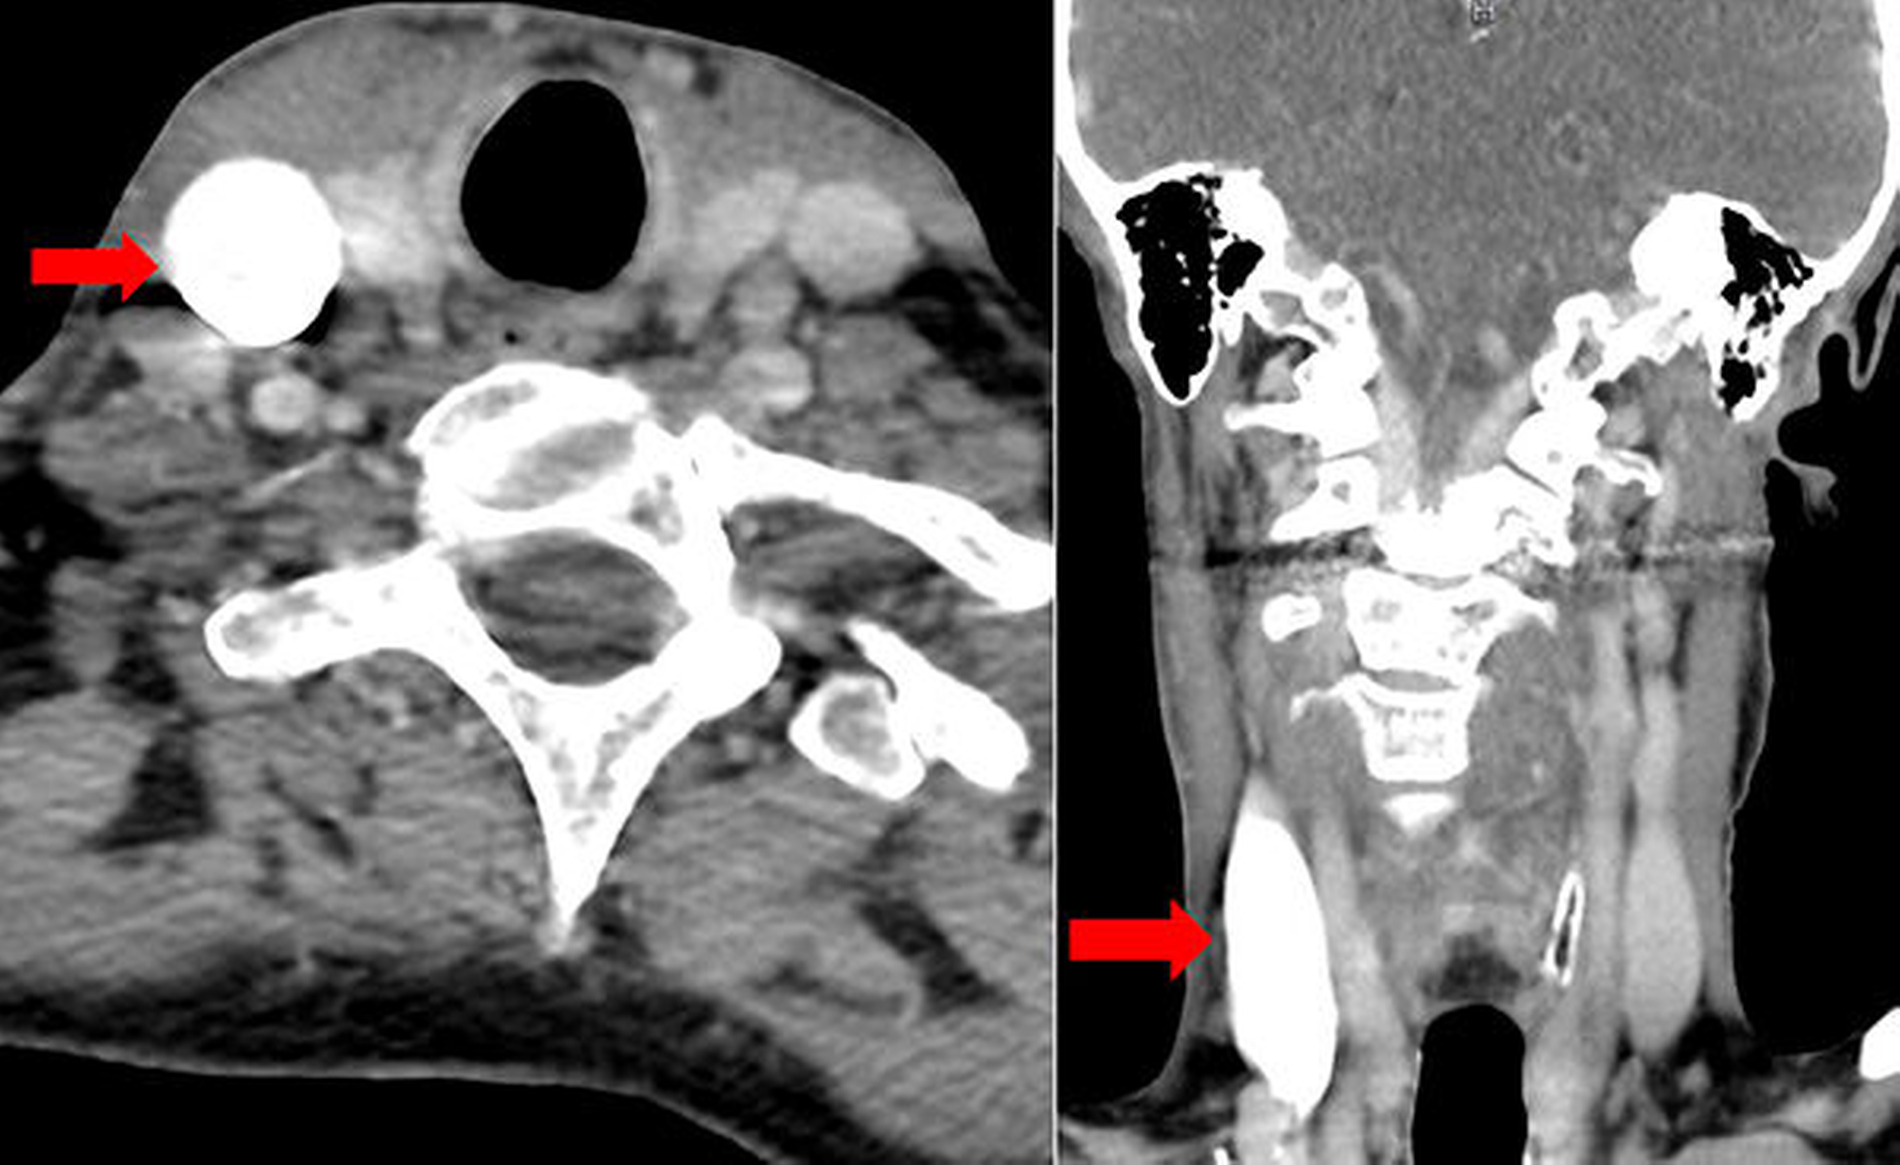

Die durchgeführten laborchemischen Untersuchungen zeigten eine Erhöhung des C‑reaktiven Proteins auf 6,6 mg/dl sowie am Vorstellungstag eine normwertige Leukozytenzahl. Zur weiteren Diagnostik erfolgte eine Computertomografie des Kopf- und Halsbereichs mit Kontrastmittel. Hierbei zeigte sich eine Thrombosierung der V. jugularis interna rechts (Abbildung 3).